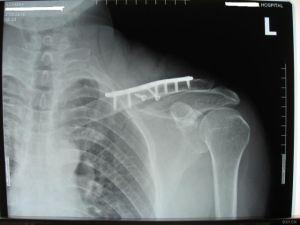

4.手术治疗

手术治疗指征包括开放骨折;合并血管、神经损伤的骨折;有喙锁韧带断裂的锁骨外端或外1/3移位骨折;骨折不连接。内固定方法可视骨折的类型和部位等不同,选择“8”字钢丝、克氏针或钢板螺钉固定。

锁骨骨折内固定术后